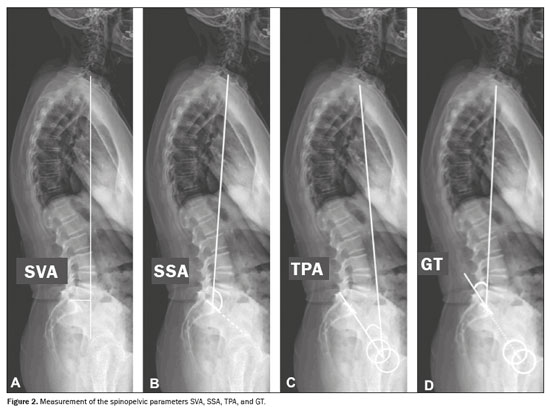

To measure the spinopelvic parameters and vertebral curvature angles, we used Surgimap software (Nemaris Inc., New York, NY, USA). The following parameters were evaluated (Figures 1 and 2): sacral slope (SS); pelvic tilt (PT); pelvic incidence (PI); lumbar lordosis (LL); thoracic kyphosis (TK); sagittal vertical axis (SVA); spinosacral angle (SSA); T1 pelvic angle (TPA); and global tilt (GT). The SS corresponds to the angle formed between the upper endplate of S1 and a horizontal line. The PT corresponds to the angle formed between a vertical line originating at the center of the femoral head and a line running from the center of the femoral head to the midpoint of the S1 endplate. The PI corresponds to the angle formed by a line running perpendicular to the sacral plateau and a line connecting its midpoint with the center of femoral rotation. The degree of LL is determined by measuring the Cobb angle from the superior endplate of S1 to the superior endplate of L1. The degree of TK is determined by measuring the Cobb angle from the inferior endplate of T12 to the superior endplate of T1. The SVA is the measurement of the horizontal distance between the plumb line of C7 and the vertical line passing through the posterosuperior point of S1. The SSA corresponds to the angle formed between the line passing from the center of C7 to the center of the endplate of S1 and the surface of the sacral endplate. The TPA corresponds to the angle formed by a line running from the geometric center of the femoral heads to the center of the T1 vertebral body and a line running from the geometric center of the femoral heads to the center of the superior endplate of S1. The GT is defined as the angle formed by a line running from the center of the superior sacral endplate to the center of the C7 vertebral body and a line running from the geometric center of the femoral heads to the center of the sacral endplate(15). The contours of the femoral heads were marked, and lines were drawn adjacent to the superior plateau of S1, superior plateau of L1, inferior plateau of T12, superior plateau of T1, and inferior plateau of C2. From those markings, the software automatically calculated the spinopelvic parameters and vertebral curvatures.